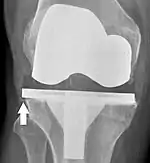

Loosening of the prosthesis can be indicated on X-ray by thin radiolucent spaces around the implant, or more obviously by implant displacement.[50]

Knee replacement is routinely evaluated by X-ray, including the following measures:

- FFC: frontal femoral component angle. It is typically regarded as optimal when being 2–7° in valgus.[57]

- FTC: frontal tibial component angle, which is regarded as optimal when being at a right angle. A varus position of more than 3° has generally been found to increase the failure rate of the prosthesis.[57]